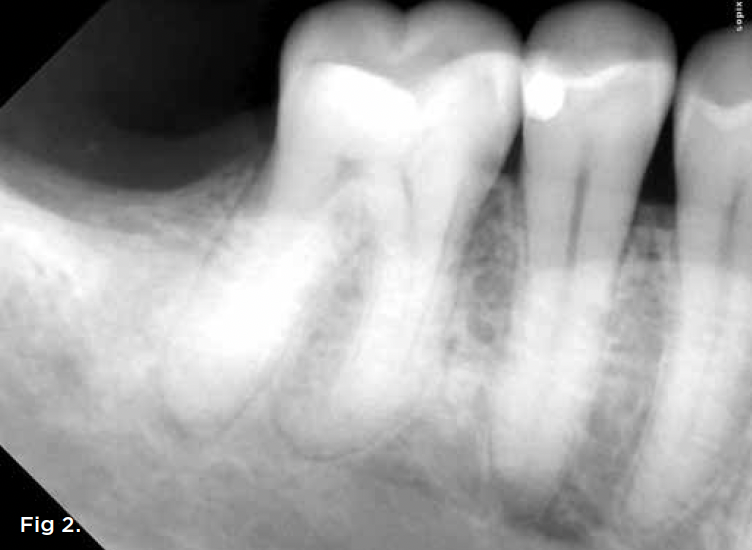

The extent of any crestal bone defects can impact recommendations. Teeth with extensive crestal bone defects whose further enlargement would complicate future implant replacement, for example, might be better suited to extraction. When discussing such issues with patients, the conversation should be detailed and accompanied by visual aids such as radiographs and/or illustrations, and include a thorough review of risks and benefits in both the short and long term. A case of fracture necrosis and periapical infection is presented in Figure 2 and Figure 3. Figure 1, to reiterate, summarizes the proposed treatment algorithm for unseparated fractures.

Fig 2. A 63-year-old male patient presented with a chief complaint of spontaneous pain and pressure discomfort of 3-week duration. A distal fracture line was visible on tooth No. 30, with a localized 7 mm deep periodontal probing depth adjacent to its distal aspect. The tooth had no response to pulp sensitivity testing and was sensitive to percussion. Periapical imaging (Fig 2) revealed a tooth with a shallow restoration and early signs of apical pathology. CBCT imaging (Fig 3, axial view, top left; and sagittal view, bottom right) confirmed early signs of apical pathology and showed localized crestal bone loss adjacent to the distal fracture line. A diagnosis of pulpal necrosis with symptomatic apical periodontitis was made, and the fracture was determined to involve root structure given the periodontal findings and radiographic crestal bone loss noted. The patient elected to pursue extraction with implant replacement given the reduced long-term prognosis for maintenance of the tooth.

Fig 3. A 63-year-old male patient presented with a chief complaint of spontaneous pain and pressure discomfort of 3-week duration. A distal fracture line was visible on tooth No. 30, with a localized 7 mm deep periodontal probing depth adjacent to its distal aspect. The tooth had no response to pulp sensitivity testing and was sensitive to percussion. Periapical imaging (Fig 2) revealed a tooth with a shallow restoration and early signs of apical pathology. CBCT imaging (Fig 3, axial view, top left; and sagittal view, bottom right) confirmed early signs of apical pathology and showed localized crestal bone loss adjacent to the distal fracture line. A diagnosis of pulpal necrosis with symptomatic apical periodontitis was made, and the fracture was determined to involve root structure given the periodontal findings and radiographic crestal bone loss noted. The patient elected to pursue extraction with implant replacement given the reduced long-term prognosis for maintenance of the tooth.

Figure 3